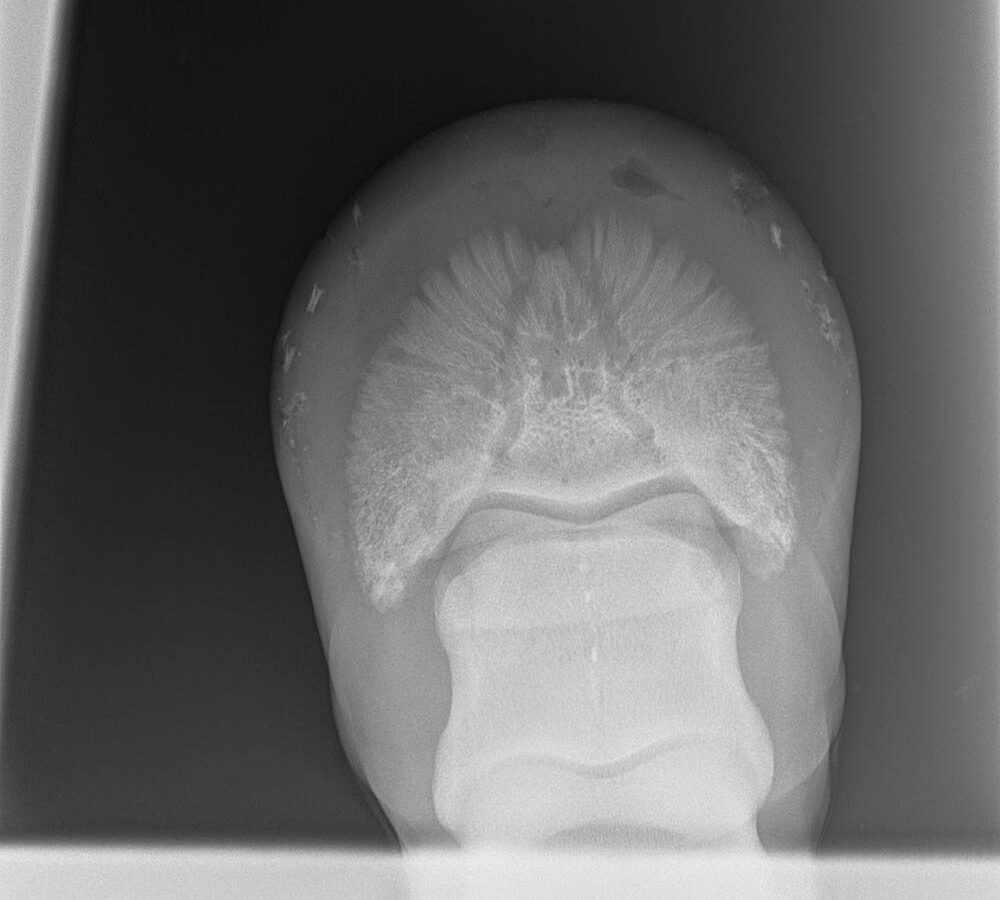

These X-rays show a black pocket near the toe of the pedal bone. © Maxine Brain.

As I had a great relationship with the farrier, we discussed the case and decided the best approach was to work together to find a solution. I was able to X-ray the foot with the farrier present and isolate a small pocket of pus (gas pocket) near the toe of the foot. The farrier was able to cut the tip of a horseshoe nail and fix it to the area of the sole that we both thought approximated the underlying gas pocket. By X-raying again and adjusting our marker, we were able to accurately pinpoint an area and the farrier was able to make a small hole directly over the abscess and allow the pus to escape. The result was a horse that was significantly sounder (and happier) the following day.